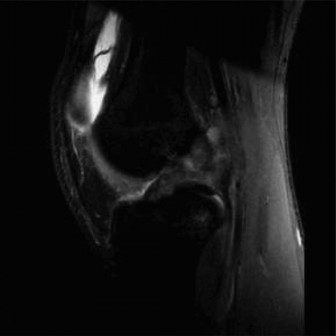

CASE 9 A 14-year-old boy is brought to the ER with complaints of right knee pa…